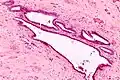

It is characterized by cysts with tubal-type epithelium (e.g. ciliated epithelium) surrounded by a fibrous stroma. It is not often associated with hemorrhage.

Intermed. mag.

High mag.

Very high mag.